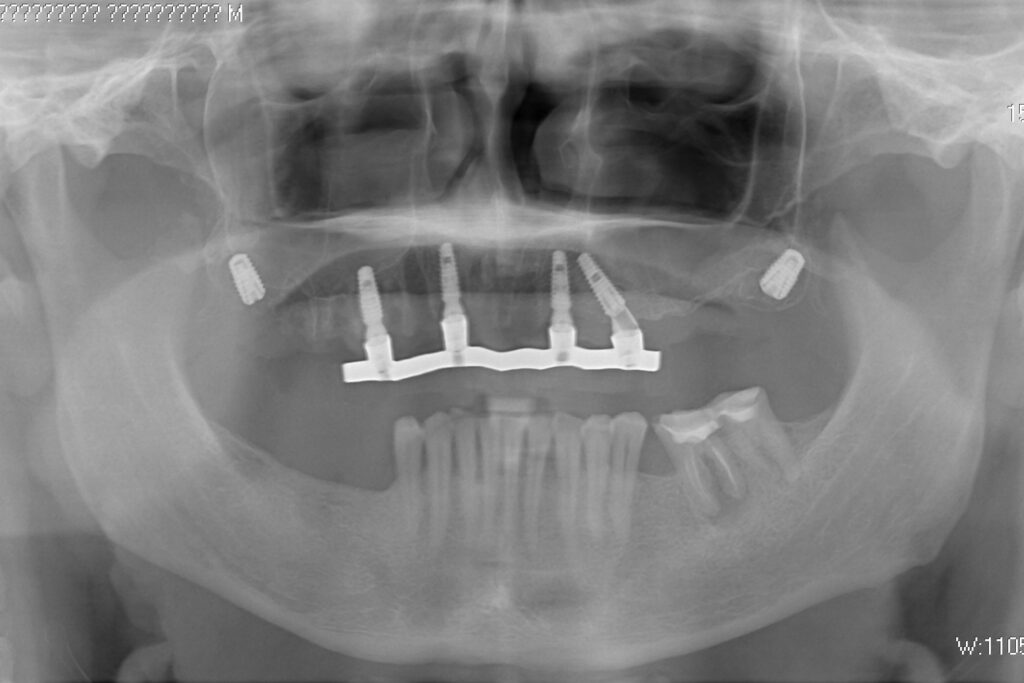

После установки 6ти имплантантов Megagen Anyone, было принято решение зафиксировать металлоакриловый протез протез на 4 имплантата.

2 крайних имплантата, установленных в бугры, были ушиты с целью дальнейшего приживления. При постоянном протезирование протез будет зафиксирован на 6ти имплантатах.

Спустя 7 дней на верхней челюсти зафиксирован металлоакриловый протез из 12 зубов с опорой на 4 дентальные имплантата.